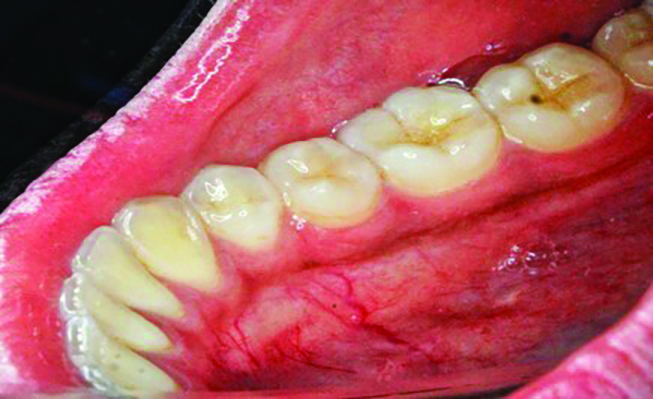

The MGJ was delineated by the visual method and the roll method following clinical examination in dental chairs appropriately equipped. Visual assessment relies on identifying the color difference between the gingiva and alveolar mucosa. The mucosa beyond the MGJ typically appears darker red compared to the AG, helping to demarcate the MGJ. The rolling probe method entails pushing the neighboring alveolar mucosa coronally with the blunt end of a probe. It is a functional assessment method that aids in determining the boundary between gingiva and movable mucosa.10 The probing sulcus depth was subtracted from the measured KG width at the mid-lingual aspect of each tooth to determine the width of AG, and all fractional measurements were rounded off to the nearest whole number of millimeters (Figure 1 through Figure 3).

Table 1 presents descriptive statistics for the demographic characteristics of the participants: 83.33% of the study population were aged 18 to 24 years, while 16.66% were aged 25 to 30 years, and 20% of the participants were male while 80% were female, indicating a skewed distribution. Figure 4 through Figure 6 illustrate lingual AG of a representative male subject, and Figure 7 through Figure 9 depict that of a female subject. The mean, standard deviation, mode, median, and extremes for all the mandibular permanent teeth are recorded in Table 2. The extreme measurements were in the range of 0 mm to 10 mm, considering all teeth and subjects. The width of lingual AG varied with each tooth, with the mandibular first molar having the widest average width (6 mm ± 1.3 mm) followed closely by the second molar (5.8 mm ± 1.2 mm). The central incisors (0.5 mm ± 0.5 mm) showed the narrowest zone along with the highest maximum number of teeth without detectable AG (Table 3). The width of AG did not significantly differ between the sexes (Table 4). The overall indicative schematic of lingual AG is shown in Figure 10 and Figure 11.

Fig 4 through Fig 6. Lingual attached gingiva in a male subject: Fig 4 = left side.

Figure 4

Fig 5 = middle.

Figure 5

Fig 6 = right side.

Figure 6